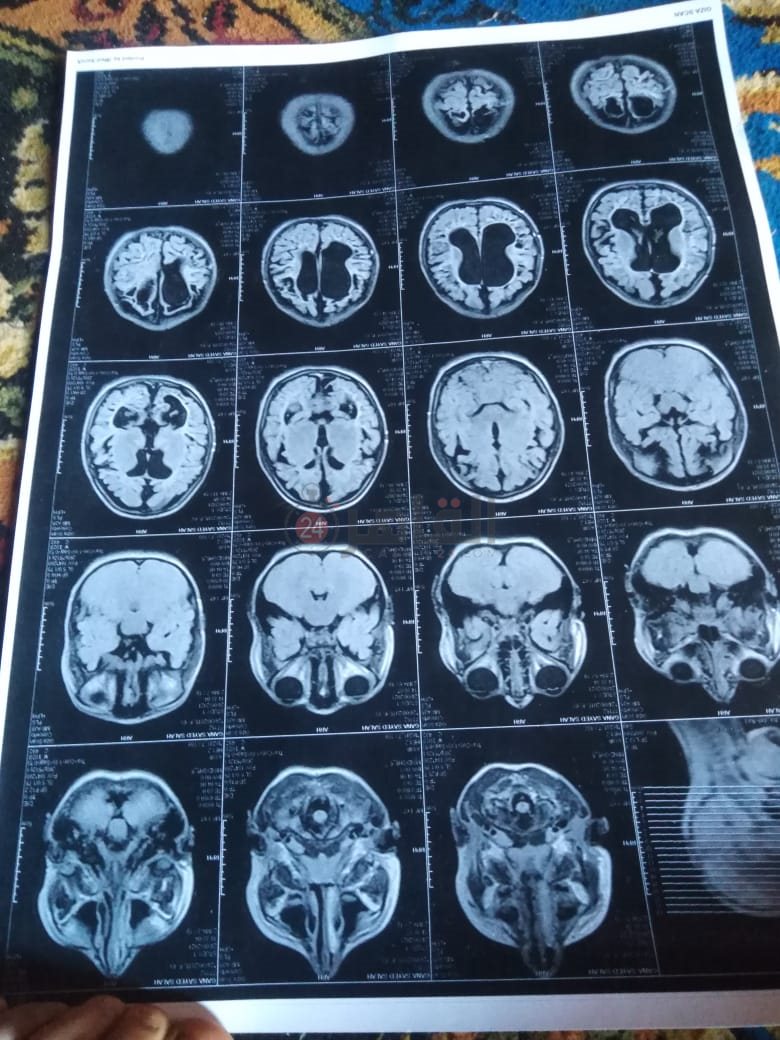

من جانبه، قال صلاح سيد، والد الطفلة جنى صلاح، إن ابنته تعاني من ضمور في المخ منذ ولادتها، نتيجة خطأ طبي، أدى إلى نقص كبير في الأكسجين لديها.

وأضاف في تصريحات خاصة لـ "القاهرة 24": "جنى تبلغ من العمر 6 سنوات، لا تستطيع المشي أو الوقوف على قدميها، نتيجة إصابتها بضمور في المخ منذ ولادتها".

وتابع: "مكنتش بتتحرك خالص، وجسمها طري، روحت كشفت عليها، وعملت أشعة وتحاليل كتير، أتأكدنا إصابتها بضمور في المخ"، مضيفًا:" مش بتعرف تأكل احنا اللي بنأكلها، هي عقلها كويس لكن مش بتتحرك ولا تتكلم".